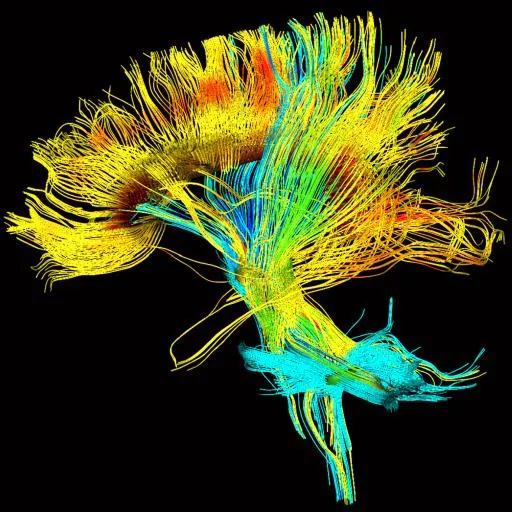

)(New PFP

)